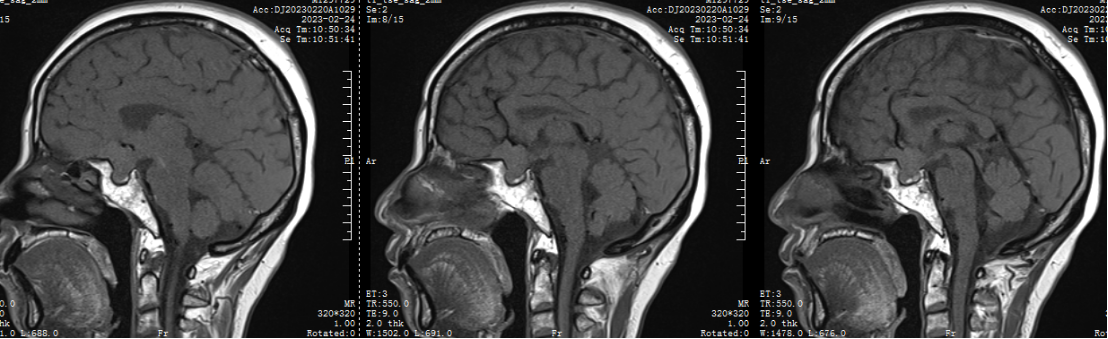

1.患者张XX,女,61岁,以“头晕2天”为主诉入院。

2.两天前患者无诱因出现头晕,伴恶心、呕吐、右眼视物模糊,无意识障碍,无发热、咳嗽、咳痰,无耳鸣、听力下降,无言语不清、饮水呛咳、吞咽困难,无颈强直,无肢体感觉及活动障碍等伴随症状,于我院门诊就行头颅CT示:腔隙性脑梗死,现为进一步诊治,遂来我院。

5.辅助检查:垂体激素水平正常

二 术前检查及会诊

鞍结节脑膜瘤(tuberculumsellaemeningioma TSMs)仅占颅内脑膜瘤的4%~10%。鞍结节脑膜瘤沿脑膜向周围生长,向前可达眶尖,向后可达斜坡及小脑幕,向外沿中颅窝底扩展,向内可累及鞍内垂体腺。常最早侵犯视神经,多以视力障碍为首发症状,产生颅高压为引起头痛、恶心、呕吐,侵犯垂体会出现垂体功能障碍相应症状。